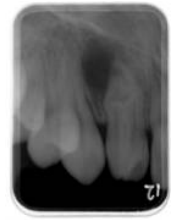

(A)External root resorption (B)Internal root resorption (C)Dens invaginatus (D)Dens evaginatus

72.下圖上顎後牙區之根尖片,靠近第一大臼齒根尖處之放射線不透過性(radiopaque)影像,最可 能之X光診斷為: